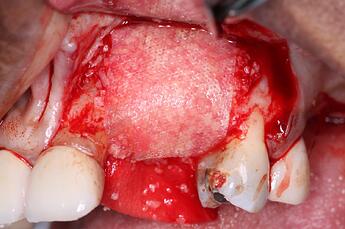

In the second part of our grafting technique, a DALI Amnion Chorion Membrane was layered over the bone graft, before we covered the entire site with a collagen membrane. The rationale for using an Amnion membrane here is that given the difficult nature of this GBR, we wanted to take advantage of the unique biological benefits of Amnion membranes, such as their inherent growth factors and anti-bacterial properties, to maximize the healing of the site and and enhance regeneration. For additional information on using Amnion membranes for this purpose, please see Enhance GBR and Improve Implant Surgical Outcomes with Amnion-Chorion Membranes